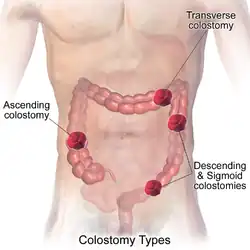

В толстой кишке человека анатомически выделяют следующие отделы:

- слепая кишка (лат. caecum) с червеобразным отростком (лат. appendix vermiformis);

- ободочная кишка (лат. colon) с её подотделами:

- восходящая ободочная кишка (лат. colon ascendens);

- поперечная ободочная кишка (лат. colon transversum);

- нисходящая ободочная кишка (лат. colon descendens);

- сигмовидная ободочная кишка (лат. colon sigmoideum);

- прямая кишка, (лат. rectum), с широкой частью — ампулой прямой кишки (лат. ampulla recti), и оконечной сужающейся частью — заднепроходным каналом (лат. canalis analis), которая заканчивается анусом (лат. anus).

Рак образуется в форме опухоли, растущей в направлении отверстия толстой кишки, или в форме отёка, сужающего это отверстие. Большинство новообразований толстой кишки появляются в последнем её участке, что значительно облегчает лечение. Достижения в области диагностики и хирургии помогают выявлять и удалять раковые опухоли на ранних стадиях.